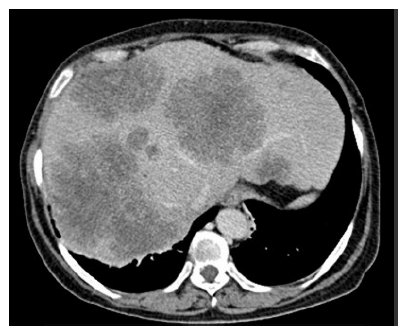

Paciente do sexo feminino, 62 anos de idade, relata dor abdominal em hipocôndrio direito há cerca de 1 mês e emagrecimento de 10 kg nos últimos 6 meses. Sem outras comorbidades. Nega história familiar de câncer de intestino. Ao exame físico: anictérica, palpada hepatomegalia dolorosa. A tomografia computadorizada de abdome evidenciou múltiplas metástases hepáticas inoperáveis e não passiveis de conversão. Tomografia computadorizada de tórax normal. CEA = 2.000 ng/ml. Colonoscopia mostrou lesão ulcerada em cólon sigmoide, ocupando 90% da luz do órgão. A biópsia da lesão em sigmoide confirmou adenocarcinoma de cólon. Pesquisa da mutação KRAS foi positiva.

Com base nesse caso clínico e nos conhecimentos médicos correlatos, julgue os itens a seguir.